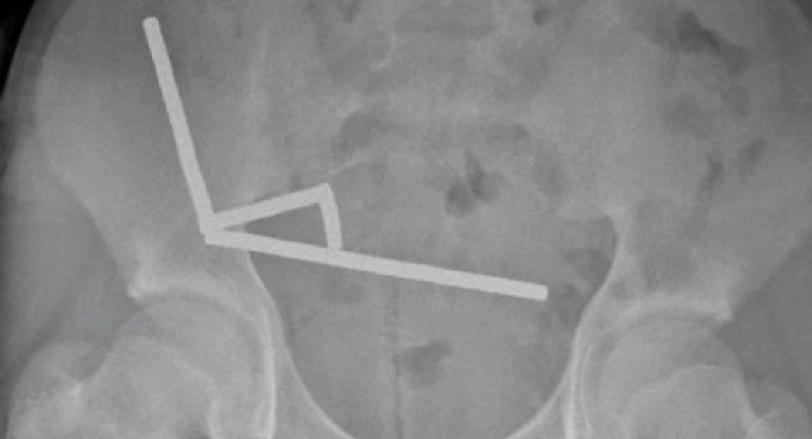

新西兰发生一起离奇医疗案例,一名13岁少年吞下多达100块从中国电商平台Temu购买的强力磁铁,腹痛难忍就医。外科医生发现少年有4处组织坏死,需手术切除部分肠道。 X光片曝光,惊现4条长直链 据报道,这名未透露姓名的少年吞下磁铁后腹痛4天,随后被送往新西兰北岛的陶朗加医院(Tauranga Hospital)治疗。X光片显示,磁铁在少年肠道不同位置因磁力吸附在一起,形成4条长直链。